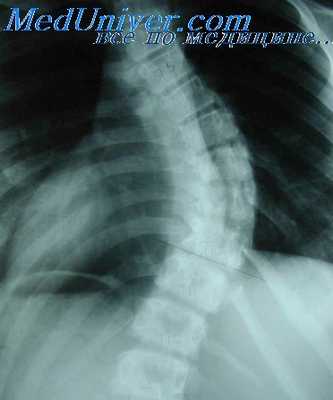

Рентгенологическая картина после торакопластики. На обзорных рентгенограммах и томограммах после экстраплевральной Т. определяется уменьшение объема оперированной половины грудной клетки и спадание соответствующего легкого. Степень уменьшения объема грудной клетки и легкого на оперированной стороне зависит от вида и объема Т. Рентгенологические изменения в легких наблюдаются при возникновении пневмонии, иногда осложняющей послеоперационное течение. В первые дни после операции могут возникать массивные ателектазы, в свою очередь осложняющиеся пневмониями. После обширной Т. может наблюдаться флотирование (маятникообразное смещение, синхронное с дыханием) средостения в области дефекта грудной стенки, исчезающее по мере регенерации костной ткани из оставшейся надкостницы ребер.

В отдаленные сроки после операции спавшееся легкое частично расправляется и вентиляция его улучшается за счет увеличения амплитуды дыхательных движений диафрагмы и ребер на стороне оперативного вмешательства, что отчетливо определяется на рентгенокимограмме (см. Рентгенокимография). В ряде случаев расправления легкого в отдаленные сроки не происходит вследствие развития в нем после операции пневмосклероза (см.), а иногда в последующем — бронхоэктазов (см.).

Определяемые после Т. тени регенерировавших ребер, особенно на фоне массивных плевральных шварт, затрудняют распознавание остаточных каверн и щелевидных остаточных полостей эмпием в случае неэффективной операции. Томография (см.) облегчает диагностику каверн в спавшемся легком, а фистулография (см.) и бронхография (см.) — выявление остаточных полостей.